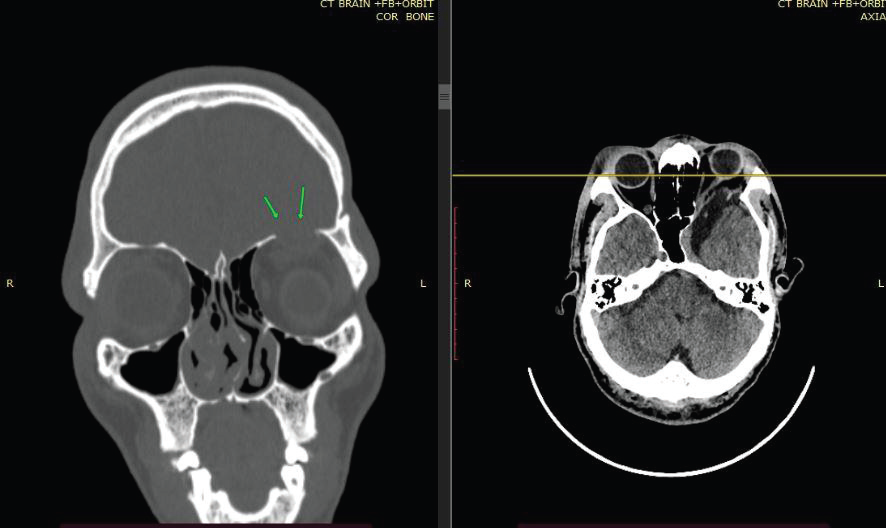

Figure 3: CT BRAIN (CORONAL AND AXIAL) OF 39-YEAR-OLD

GENTLEMAN WITH KNOWN NF-1 demonstrates hypoplasia of the left

sphenoid wing (arrow) with loss of the normal bony separation between the

middle cranial fossa and the orbit, allowing herniation of intracranial contents

into the left orbit.

CT of the skull base confirmed hypoplasia of the left sphenoid wing with loss of the normal bony separation between the middle cranial fossa and the orbit. Prior imaging studies had described the lesion as an arachnoid cyst, leading to delayed recognition of the underlying pathology.